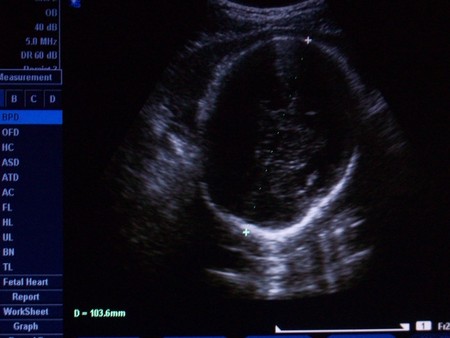

срок по М - 32,5

БПР - 89 (35нед)

Животик - 97,5 (36,5 нед)

Бедро - 64 (33н)

Большеберцовая кость - 57,3 (34,5н)

Плечо - 57,2 (32,5н)

Локоть - 52 (36н)

а тут сфотографировали нас с головы и плечики видно))